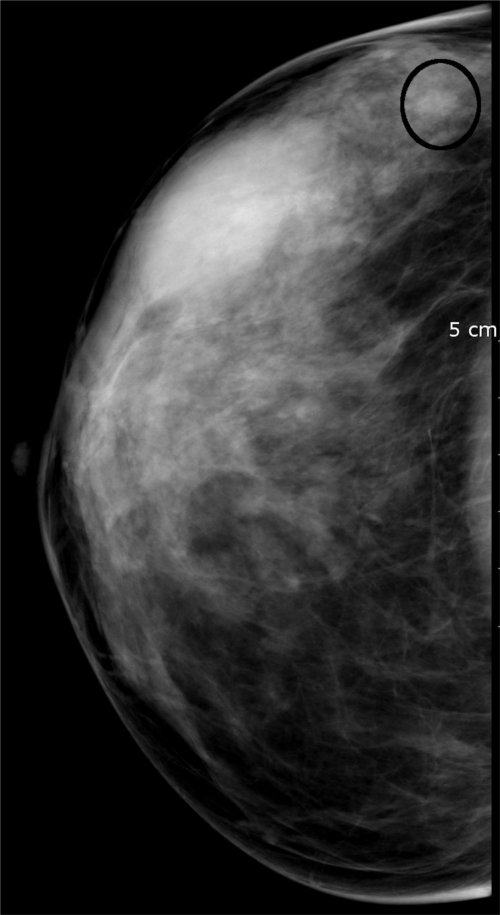

Détection assistée par ordinateur (CAD)

C'est un outil informatique sophistiqué complémentaire à la mammographie qui met en évidence les régions suspectes de l'image afin d'aider le médecin à détecter précocement une anomalie.